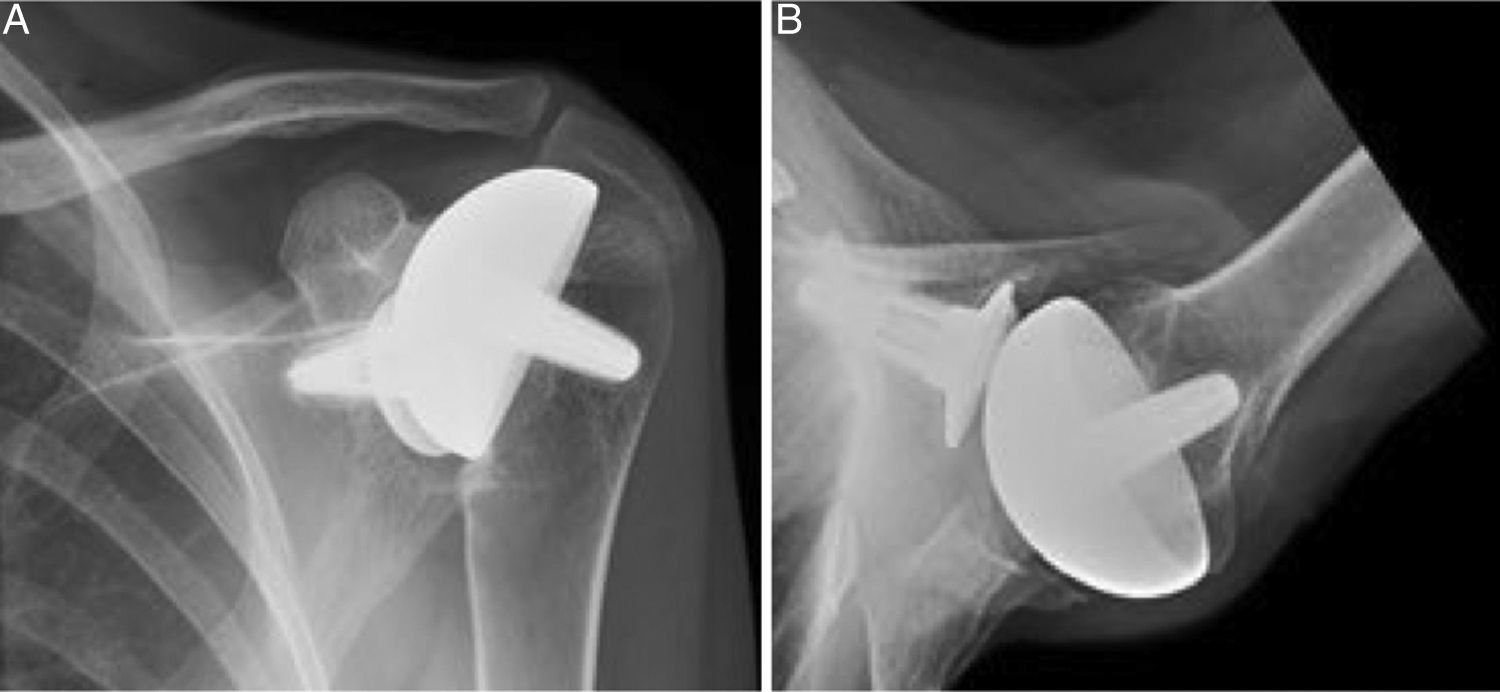

Unlike total shoulder replacement, which replaces both the ball and socket, resurfacing shoulder arthroplasty involves capping the damaged ball of the joint with a smooth, metal prosthesis. This approach is less invasive, preserves more bone, and is often ideal for younger, active patients with localized joint damage.